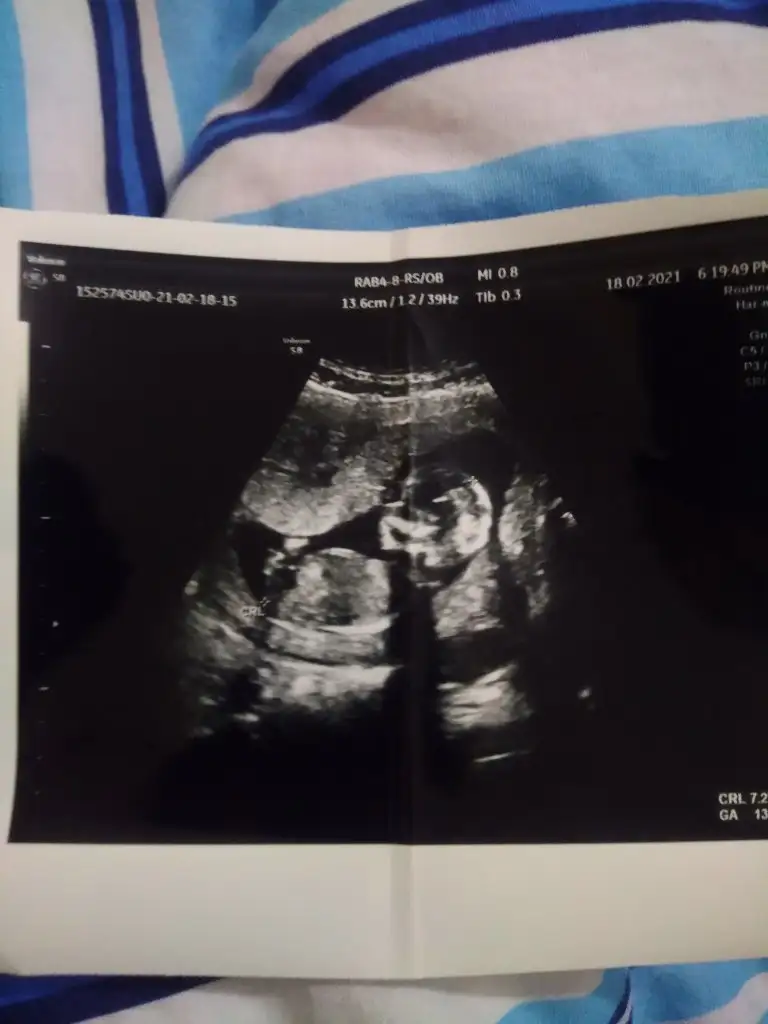

Benimde tahmin edebilir misiniz ilk resim 6 +4 günlük ikinci resim 13 +3